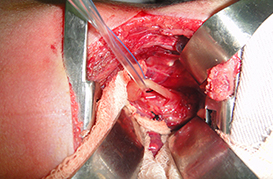

Atresia de Esofago

Atresia Intestinal

Enterocolitis

Gastrosquisis y Onfalocele

Hipertrofia de Piloro

Neo Natal y Lactante